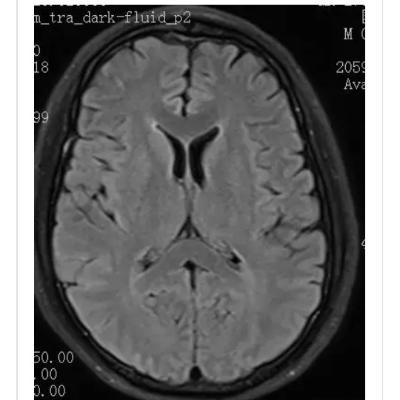

10月大婴儿,因癫痫持续状态就诊,2天前有发热和稀便。头颅MRI提示脑组织肿胀和累及丘脑,白质和背侧脑干的T2高信号病灶(图1)。丘脑病变在DWI和ADC上可见三层外观,伴有SWI上可见的局灶出血(图1-2)。 最终诊断:急性坏死性脑病 讨论 儿童急性坏死性脑病是一种爆发性脑病,主要累及婴幼儿。诱发因素包括病毒感染(流感病毒,轮状病毒,人类疱疹病毒6),免疫介导和遗传(RANBP2突变)。DWI和ADC上的三层表现和对称性丘脑受累具有特征性。